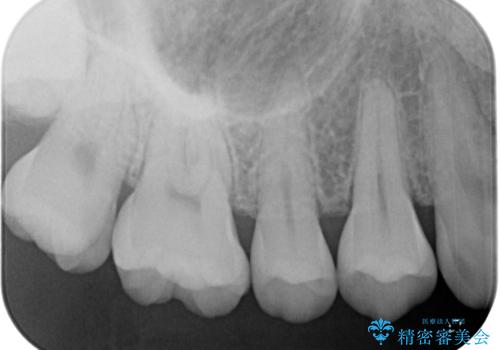

- 他院で虫歯があると言われたので診てほしいとのことで来院された患者様です。来院時特に症状もなく、レントゲンにて右上7に虫歯を認めました。

ゴールドインレー(PGAインレー)はセラミックインレーと比べ、歯の切削量が少なく、適合性が著しくいいことが特徴です。上顎の奥歯は見えないので機能面でゴールドインレー、ゴールドクラウンはおすすめです。